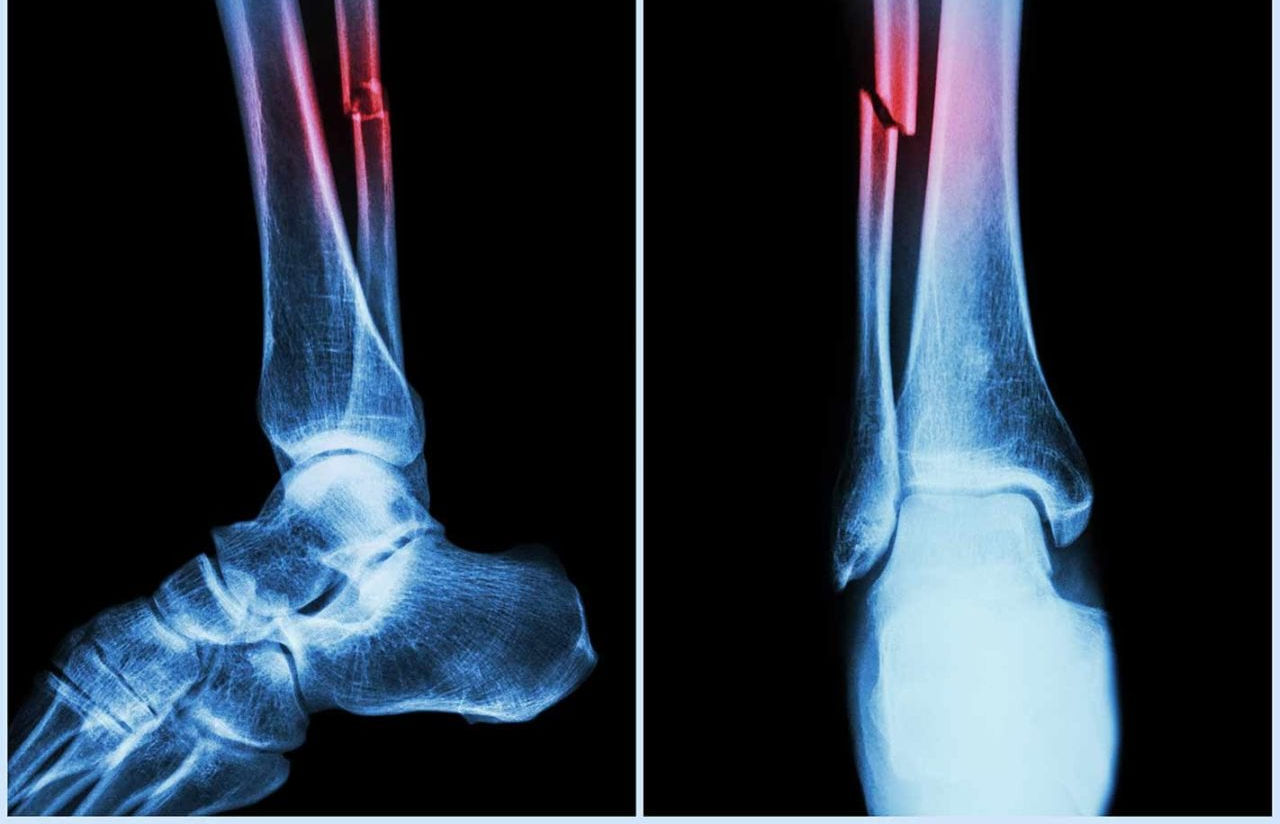

China develops injectable ‘bone glue’ for rapid fracture repair

A research team in China has reportedly developed a new type of “bone glue” that can heal fractures within minutes through a simple injection, as per reports.

Laboratory studies suggest that the adhesive, called Bone-02, demonstrated strong safety and effectiveness. It achieved a bonding force of over 400 pounds, a shear strength of about 0.5 MPa, and a compressive strength close to 10 MPa, reported Global Times.

Experts believe it could potentially replace traditional metal implants while reducing the risks of infection and foreign-body reactions. Another reported advantage is that Bone-02 can be naturally absorbed by the body as the bone heals, eliminating the need for a second surgery.